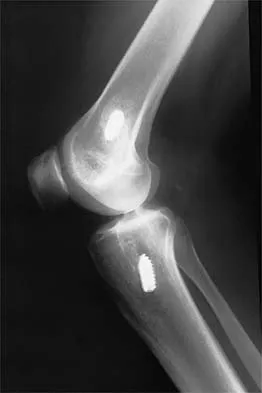

A 24-year-old runner who underwent an allograft reconstruction of the anterior cruciate ligament (ACL) 3 years ago now reports anterior knee pain. Examination reveals no swelling or effusion, and the patient has full motion. A Lachman test and a pivot-shift test are negative. Palpation reveals tenderness on the patellar tendon and at the inferior pole of the patella. AP and lateral radiographs are shown in Figures 41a and 41b. Management should consist of

Explanation